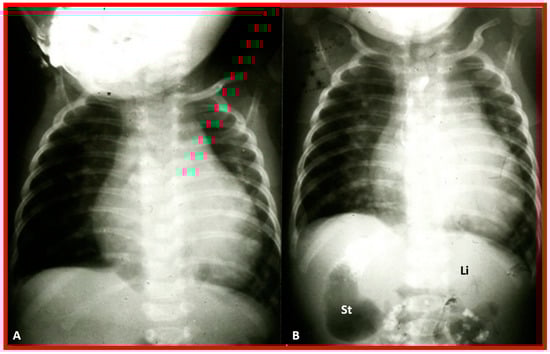

Figure 9. Chest roentgenograms of two babies with dextrocardia demonstrating liver across the entire abdomen. These babies were later diagnosed with asplenia syndrome. Umbilical venous and arterial catheters (not labeled) are seen in both (A) and (B).